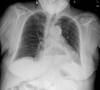

Neumonia basal derecha.

Neumonía basal derecha.